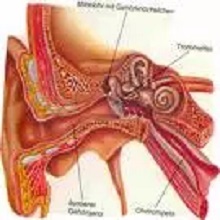

| Током викенда умерен број пацијената у ОРЛ амбуланти у Општој болници Панчево. Најчешће су долазили због компликација горњих респираторних инфекција, деца због гутања страних тела али још увек има и падова и повређивања са бицикла. |

Током лета се дешава да због незгодног скока у воду дође до пуцања бубне опне. Начелник Одељења за ухо, грло, нос доктор Вељко Божић наглашава да се треба јавити лекару и да је погрешно лечити се на своју руку, јер то може довести до оштећења слуха и операције која би могла да се избегне уколико се дође код лекара одмах после повређивања. |

„Крајници су прва одбрана и заштита од вируса и бактерија тако је било раније", напомиње начелник ОРЛ одељења доктор Вељко Божић и додаје да углавном виђају крајнике који се нису ни развили већ представљају могућност да се развијају бактеријске инфекције. Зато су међу најчешћим операције крајника на хирушком Одељењу за ухо, грло и нос |

Током два дана викенда око 100 пацијена је затражило помоћ у амбуланти на ОРЛ оделејењу Опште болнице. Поред збрињавања пацијента који су доживели саобраћајну незгоду углавном су били лаки случајеви, највише деце због упале уха. |